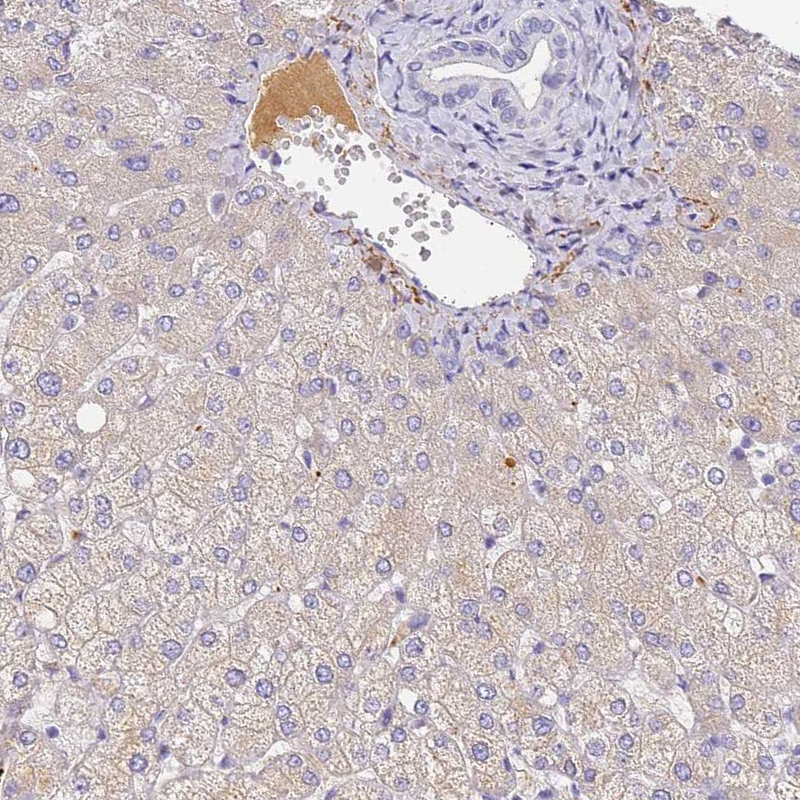

HPA038915

complement factor H-related 1

Anti-CFHR1 Antibody

Polyclonal Antibody against HUMAN CFHR1

Immunohistochemical staining of human liver cancer, hepatocellular carcinoma shows strong cytoplasmic positivity in tumor cells.